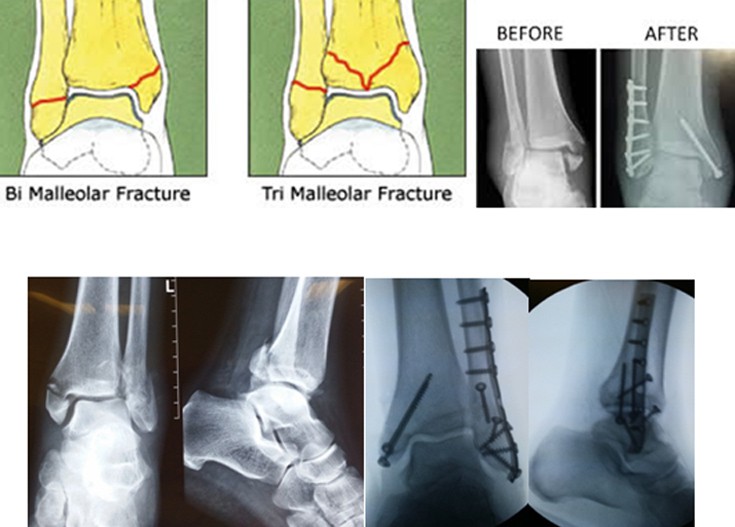

Από τα κατάγματα της ποδοκνημικής, το κάταγμα του έξω σφυρού συνήθως συνοδεύεται από κάταγμα και του έσω σφυρού (αμφισφύριο).

Η αντιμετώπιση ενός κατάγματος σφυρών, αμφισφυρίου ή τρισφυρίου (εάν έχει ξεκολλήσει κι ένα κομμάτι του πίσω τμήματος της κνήμης) είναι χειρουργική, ώστε να αναταχθεί το εξάρθρημα και να επανέλθει η ανατομική της άρθρωσης.